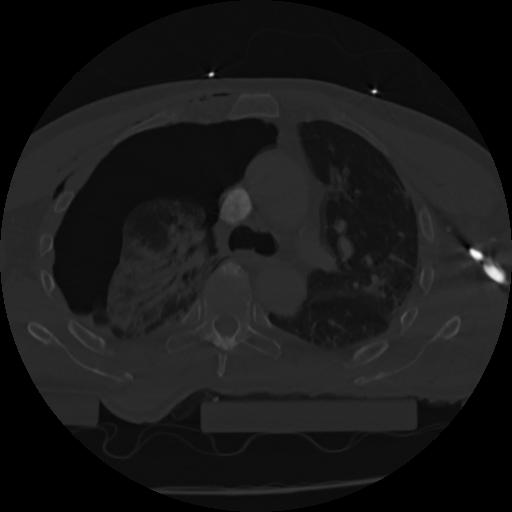

22 ANGIO,CE,Vol,0.5,ANGIO,,